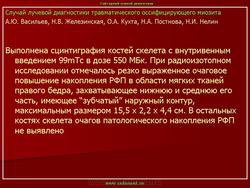

Описывается клинический случай редкого заболевания — оссифицирующего миозита — у девочки 11 лет. Представлены данные литературы, касающиеся этого заболевания.